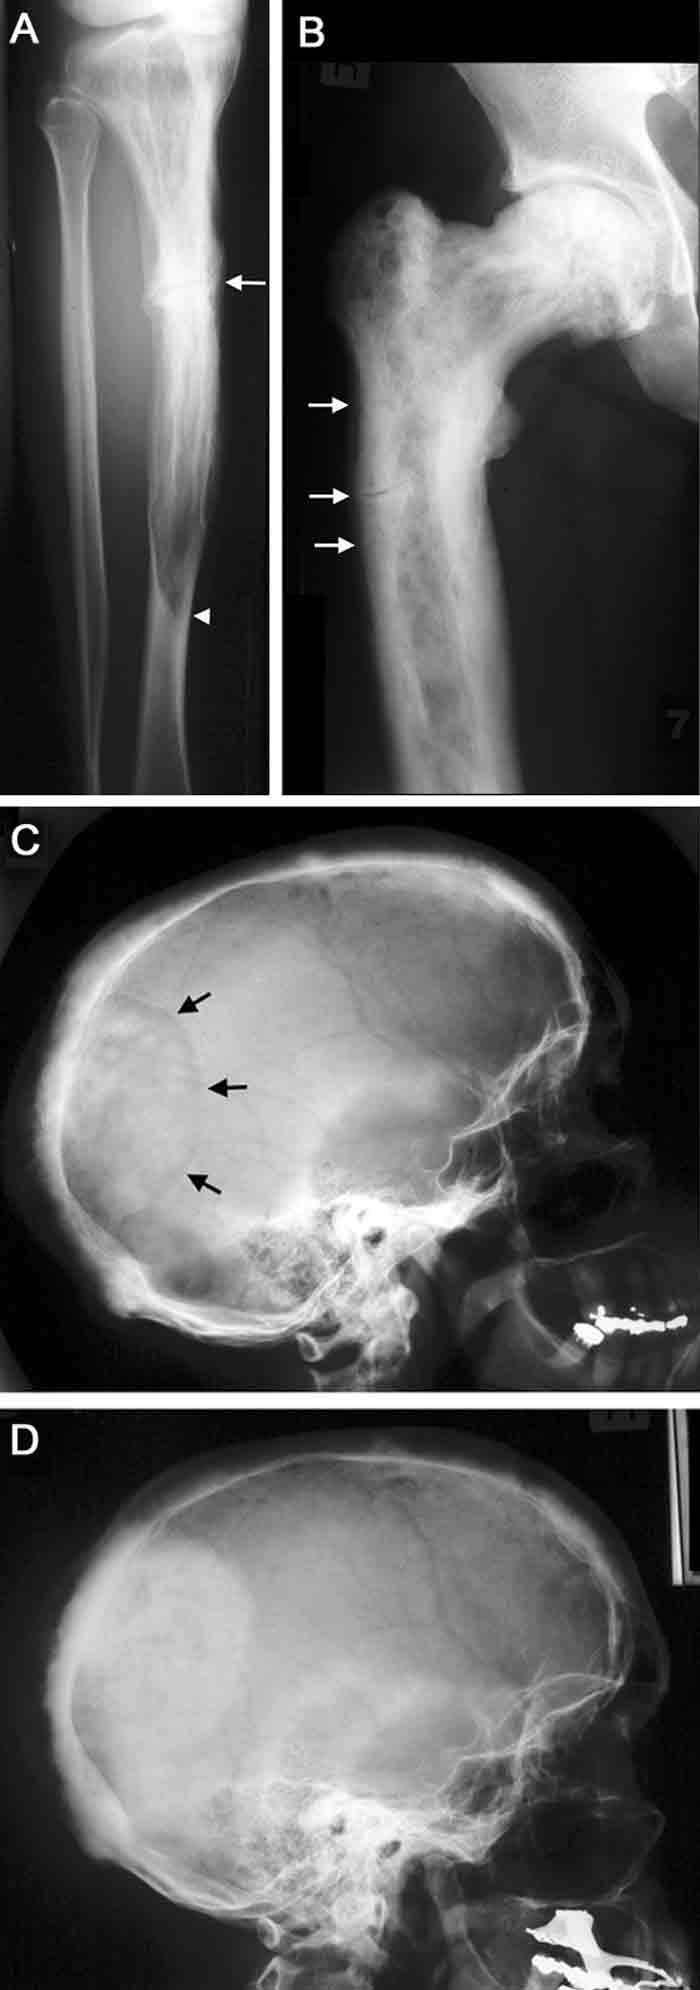

2 Radiographic features of Paget’s disease

A. Paget’s disease of the tibia, with a flame-shaped lytic wedge (arrowhead) and a pathological fracture (arrow).

B. Longstanding Paget’s disease of the femur, with bone expansion, trabecular thickening, mixed lytic and sclerotic areas, and fissure fractures (arrows).

C. Active Paget’s disease of the skull, with marked cortical thickening and an area of osteoporosis circumscripta (arrows).

D. The same patient some years later (after bisphosphonate treatment), with the lytic lesion largely replaced by sclerotic bone.